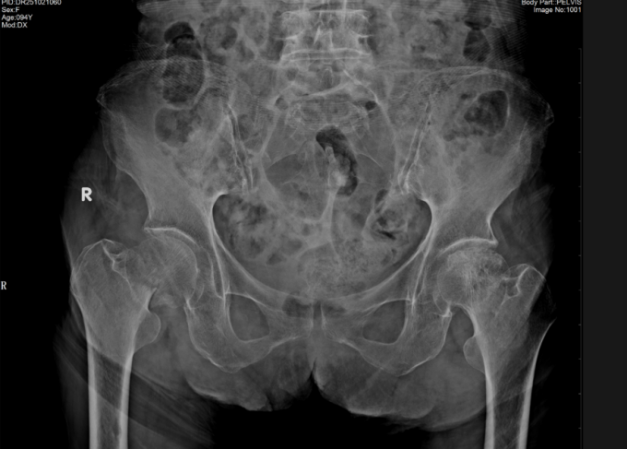

两位老人的病情均属老年关节手术中的“高危难题”,却各有核心痛点。94岁患者因意外摔倒致右侧股骨颈骨折,这种骨折被称为老年人“人生最后一次骨折”——若不及时手术,长期卧床易引发肺部感染、静脉血栓等并发症,甚至危及生命。加之患者合并高血压、冠心病、呼吸衰竭,心肺功能薄弱等,手术耐受性远低于普通人群。

手术中,骨外一科(脊柱、关节、骨病、运动医学)团队针对两位患者的不同痛点,精准施术、高效攻坚。为94岁患者实施人工髋关节置换术时,团队从切口显露、股骨取出,到假体植入,每一步都精准操作,仅50分钟顺利完成手术。为77岁患者开展全膝关节置换术时,团队严格把控截骨角度、精细调整软组织平衡,精准安装假体,手术历时1.5小时,出血量仅200ml,远低于常规水平,最大程度降低了患者创伤。

手术成功只是起点,术后康复是回归正常生活的关键。护理团队为两名患者量身定制康复计划,从早期被动活动到后期行走训练,全程精细化指导。恢复速度远超预期:94岁患者术后第3天即可借助助行器下床并缓慢行走;77岁患者术后第3天,疼痛评分(VAS评分)从8分降至2分,术后两周便能独立完成日常动作,顺利康复出院。